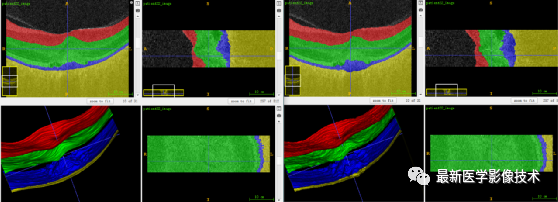

5、验证集分割结果

验证集平均结果